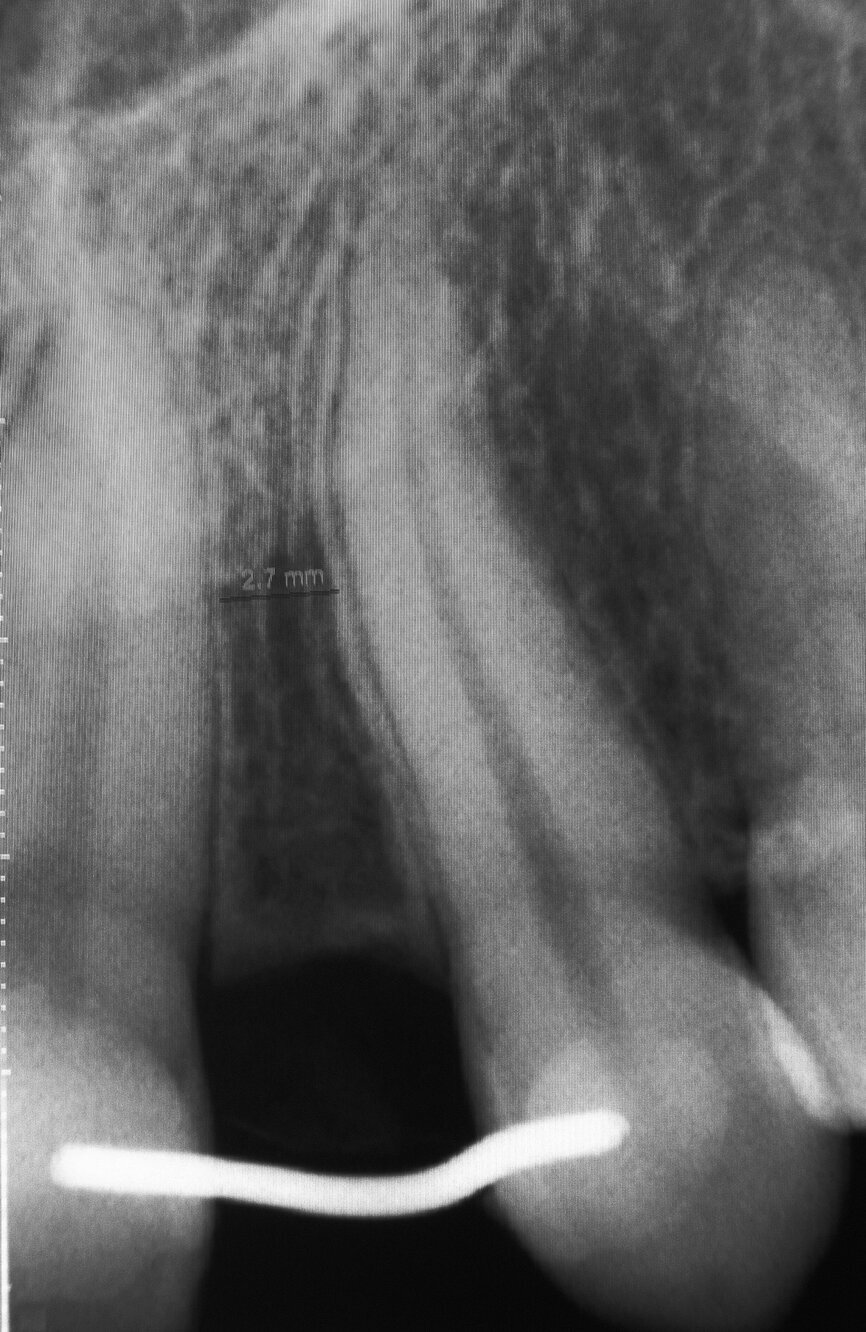

Une jeune femme de 21 ans, en bonne santé, nous a consultés pour un problème d’agénésie de l’incisive latérale gauche maxillaire. Elle avait suivi un traitement orthodontique durant trois ans au bout duquel l’orthodontiste n’avait pu obtenir qu’un espace mésio-distal de 4 mm entre le point de contact mésial de la canine supérieure gauche et le point de contact distal de l’incisive centrale gauche maxillaire. L’analyse de la radiographie périapicale numérique a montré qu’au-delà des six premiers millimètres sous le niveau de l’os crestal, 2,7 mm seulement séparaient les racines des deux dents, et après 8 mm, la distance n’était plus que de 2,1 mm (Fig. 2). Nous avons conseillé un second traitement orthodontique à la patiente, mais elle a refusé et nous avons donc discuté de la pose d’un implant étroit par la technique d’ouverture de l’espace inter-radiculaire. L’implant avait un diamètre de 3 mm, une longueur de suivantes : implant Press-Fit inséré dans l’ostéotomie ; design en plateau sans filetage ; épaulement incliné assurant un diamètre inférieur au niveau du col (selon le concept dit du « platform-switching ») ; positionnement sous-crestal à 1–3 mm sous le niveau de l’os crestal. La patiente a été anesthésiée par une injection d’articaïne et d’épinéphrine (Septocaïne, Septodont), et une légère incision crestale au moyen d’une lame de bistouri de 15c a été réalisée. Le foret-guide a été utilisé à une vitesse de rotation de 1 100 tr/min afin de perforer l’os cortical jusqu’à une profondeur approximative de 4 mm. Un alésoir manuel de Ø 2,5 mm puis un second de Ø 3 mm ont été utilisés pour effectuer pour ouvrir l’espace entre les racines.3, 4

Fig. 2 : Radiographie périapicale du site de l’agénésie de l’incisive latérale gauche maxillaire. L’espace entre les racines des dents 21 et 23 est toujours problématique après le traitement orthodontique.